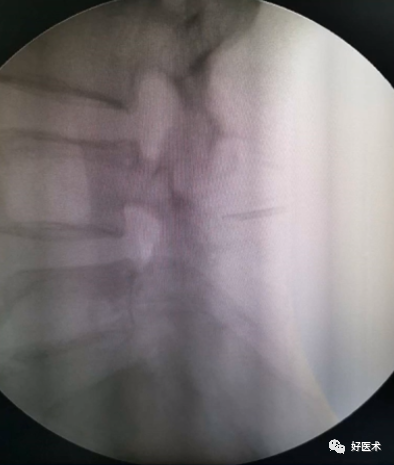

透视判断椎管

透视腰椎正位:上下终板成单边;椎弓根(猫眼)对称;棘突居中。

透视腰椎侧位:上下终板成单边;椎弓根上下缘单边;椎体后缘成单边。

实际情况:没有专业的手术透视工作人员;正位和地面垂直;侧位和患者垂直;正位看猫眼内外,侧位看椎弓根上下。

判断:透视正位,椎管外的长度设定为A;透视侧位,椎体外的长度设定为B;如果A大于或者等于B,定位针不在椎管内;如果A明显小于B,定位针在椎管内。

透视结果(优秀):①正位:定位针在猫眼内;②侧位:定位针在椎弓根正中,和椎体轴向平行;③目标椎体正确。

透视结果(及格):①正位:定位针突破猫眼内缘;②侧位:定位针在椎体内,方向和轴线不平行,预计椎弓根螺钉不会突破椎体;③目标不明确。

透视结果(调整):

①开口位置(定位针的尾部)靠内:向外侧再次开口;

②外展角度过大:应用开路锥调整外展角度;

③重新开口和调整外展角度;

④开口位置(定位针的尾部)靠下或者上,调整位置;

⑤角度过大:应用开路锥调整角度;

⑥重新开口和调整角度。